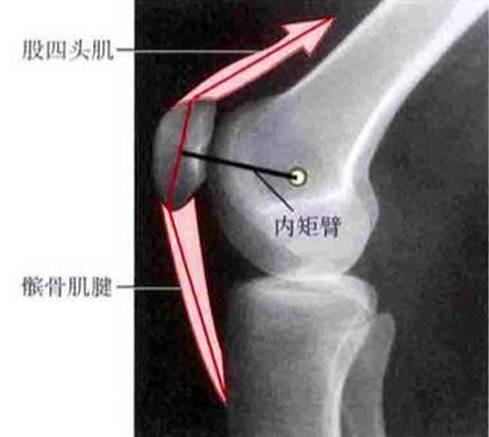

肌力不平衡:股内侧肌是髌骨的内侧动力稳定结构,如果肌肉萎缩或发育不良同样会导致髌骨向外滑动。股外侧肌过强或还有髂胫束过紧会导致髌骨向外倾斜,并在髌股关节的外侧产生过大的压力。